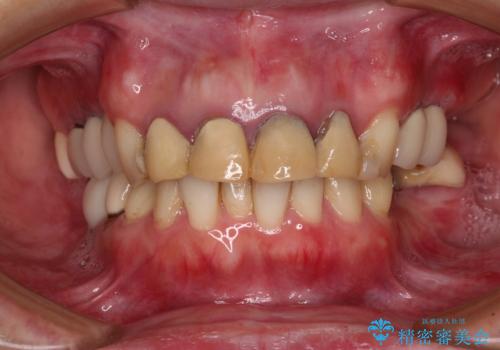

- 仮歯装着後に放置してしまい、恥ずかしいとのことで来院された患者様です。

仮歯が不適合で歯肉が腫脹していたため、しっかりと調整した新しい仮歯にして腫れを改善した上で、オールセラミッククラウンにて補綴することとしました。

日頃の歯磨きをしっかりと行ってくださるので、新しい仮歯に変えてから速やかに歯肉の状態が改善されました。

歯肉からの出血がほとんどないため精度の良い型取りができ、非常に適合の良い補綴治療を行うことができました。